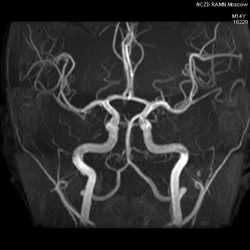

В ангио графическом режиме томограф может не только показать кровеносные сосуды, но и ток крови в динамике. Специальные программы позволяют создать трехмерное изображение всей кровеносной сети головного мозга и отдельно отобразить артериальные и венозные кровотоки. Такая модель дает возможность оценить динамику снабжения мозга кровью и выявить малейшие отклонения в этом процессе. Особенно эффективна. МРТ с ангиографией при наблюдении инсультных состояний. Стенозы, мальформации артериально венозного типа, аневризмы очень хорошо видны на срезах различных проекций без применения контрастирующего вещества. МРТ ангиографии сосудов головного мозга и шеи этого не требует в большинстве случаев. Исключение составляют исследования онкологического характера, когда параллельно с состоянием системы кровотока выявляются опухоли и метастазы.

МРТ головного мозга в ангиорежиме это покажет с большой степенью достоверности. В ангио графическом режиме томограф может не только показать кровеносные сосуды, но и ток крови в динамике. Специальные программы позволяют создать трехмерное изображение всей кровеносной сети головного мозга и отдельно отобразить артериальные и венозные кровотоки. Такая модель дает возможность оценить динамику снабжения мозга кровью и выявить малейшие отклонения в этом процессе. Особенно эффективна. МРТ с ангиографией при наблюдении инсультных состояний. Стенозы, мальформации артериально венозного типа, аневризмы очень хорошо видны на срезах различных проекций без применения контрастирующего вещества. МРТ ангиографии сосудов головного мозга и шеи этого не требует в большинстве случаев. Исключение составляют исследования онкологического характера, когда параллельно с состоянием системы кровотока выявляются опухоли и метастазы.